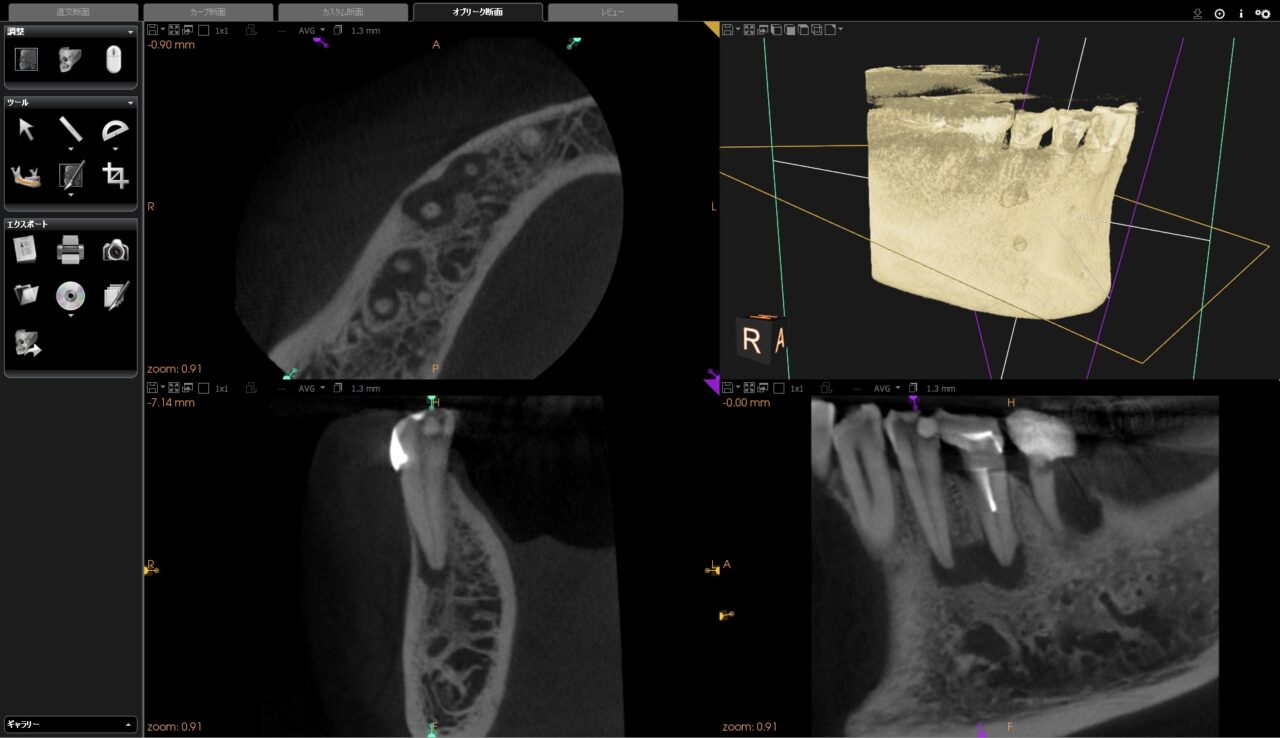

■術前のCT画像

抜髄したのは#44。感染根管処置を行ったのは#45です。

共に同日に根管充填まで終了して、次回アポイント時にファイバーポストを築造する予定になっています。